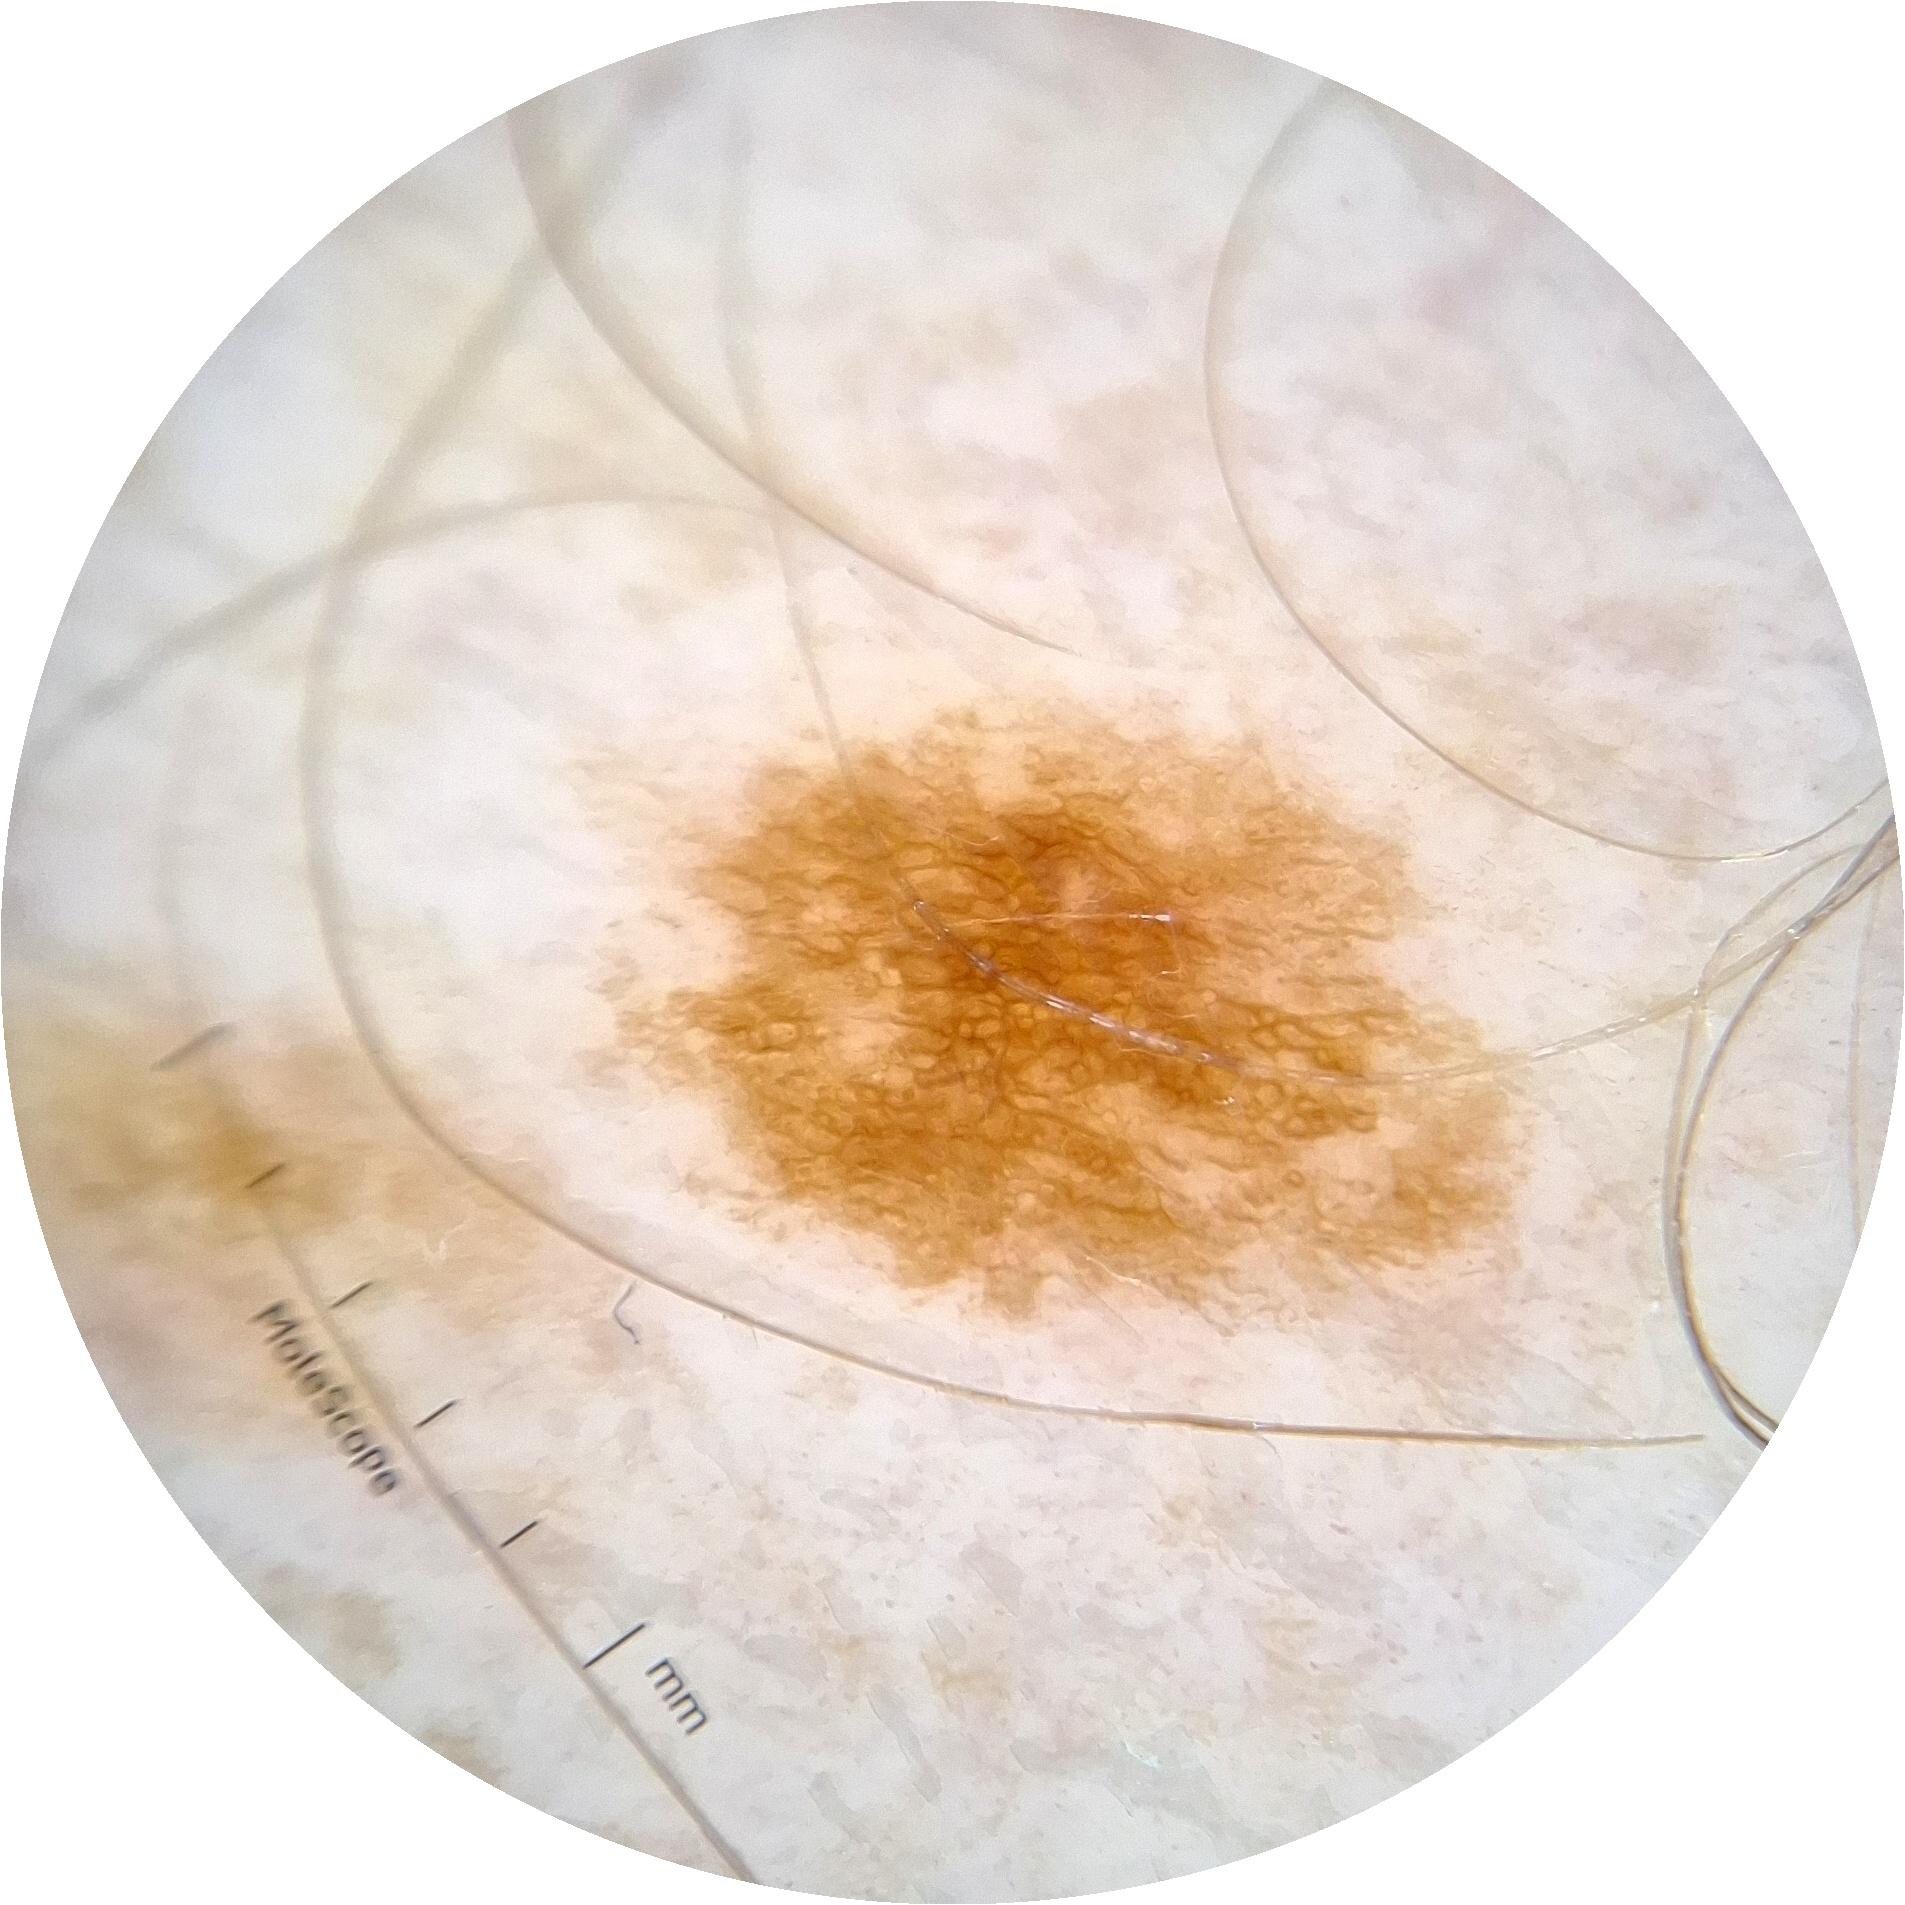

ISIC_6813604

MEL-SELF Trial, https://www.sydney.edu.au/medicine-health/our-research/research-centres/melself-project.html

acquisition_day 624

age_approx 75

anatom_site_1 Head and neck

anatom_site_general head/neck

diagnosis_1 Benign

diagnosis_confirm_type single image expert consensus

fitzpatrick_skin_type I

image_type dermoscopic